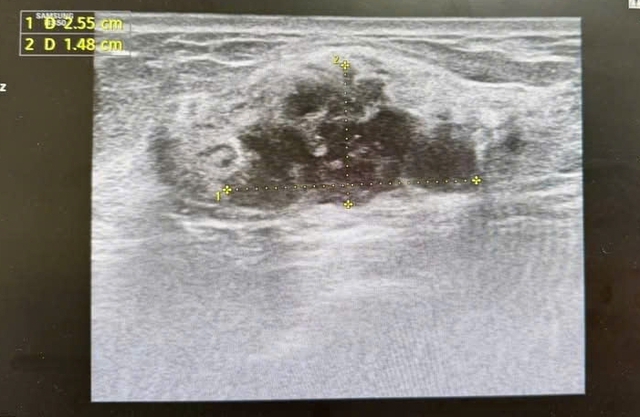

Hình ảnh khối u được phân loại BIRADS 4 trên siêu âm và chụp X-quang tuyến vú.

Các xét nghiệm tiếp theo, bao gồm chọc hút tế bào, xác định người bệnh mắc ung thư biểu mô tuyến vú giai đoạn sớm.

Theo bác sĩ, khối u ở vị trí sâu và kích thước nhỏ nên rất khó phát hiện nếu chỉ dựa vào cảm nhận thông thường. Nếu không thực hiện khám sức khỏe định kỳ, bệnh có thể chỉ được phát hiện khi đã xuất hiện triệu chứng rõ ràng hơn.